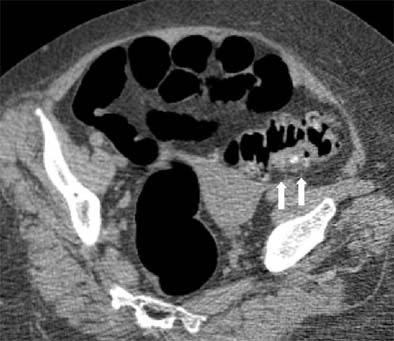

| Supine view: severe diverticulosis with global wall thickening and impacted diverticulum on the posterior aspect (white arrows). |

"Imaging findings are unequivocal when it presents as a hyperdense ring with a hypodense center on the axial images," the group wrote, adding that other researchers have reported different manifestations of impacted diverticula, such as barium or air attenuation, which did not render the findings equivocal.